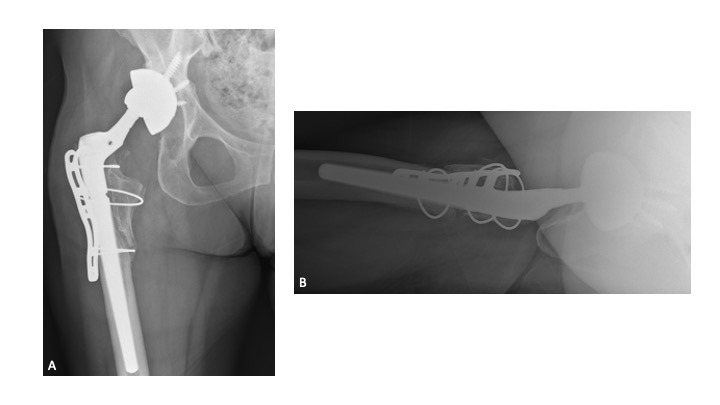

A 63-year-old female presented with recurrent THA instability - verbal consent was obtained for this report. She underwent L2-S1 posterior stabilization with L2-L3 anterior lumbar interbody fusion in May 2002 (Figure 1) and an uncomplicated right THA in April 2007. (Figures 2a-b) Five years following primary THA (July 2011), the patient sustained her first THA dislocation, which was treated with a closed reduction. Between 2011 and 2018, the patient had seven repeat episodes of hip instability – in 2012, one was complicated by a peri-prosthetic femur fracture requiring three revisions and reconstruction with a trochanteric claw plate. She was subsequently diagnosed with a prosthetic joint infection (PJI) which required an antibiotic spacer and subsequent re-implantation three months later. (Figures 3a-b) Following treatment of initial instability and femur fracture, the implants included a size 16 standard taper femoral stem and a 50-mm acetabular shell with 32-mm liner.

Twelve-weeks following re-implantation (2018), the patient experienced recurrent THA instability and was transitioned to our care for definitive treatment. At this time, the patient had a BMI of 24.22 kg/m2 and a past medical history of hypertension, rheumatoid arthritis, gastroparesis, hypothyroidism, and iron deficiency anemia. Relevant prescription medications included calcium carbonate, cholecalciferol, cyclobenzaprine, diltiazem, gabapentin, levothyroxine, and lisinopril. In August 2018, the patient underwent right THA acetabular revision with a porous titanium acetabular shell (56-mm) and dual mobility acetabular liner (44-mm), with four screws (30-mm x 2; 25-mm x 2) for adjuvant fixation. The existing stem was well-fixed and left in place, and a 44-mm/28-mm (+6) ceramic taper sleeve head was impacted. (Figures 4a-b) The patient followed a normal post-operative course and was ambulating pain free without assistance.